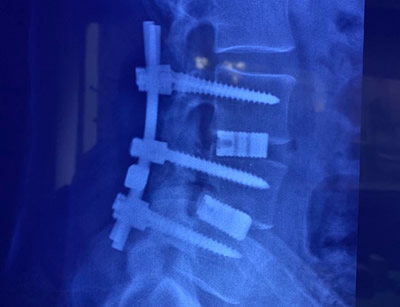

IMÁGENES

Galería de imágenes